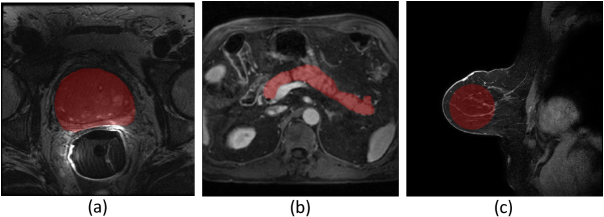

4.4 Evaluations Metrics

To comprehensively evaluate the effectiveness of the proposed bias field correction, we employ a diverse suite of quantitative metrics grouped into three categories. Intensity variation metrics include the coefficient of variation (CV) [24]. A lower CV indicates improved tissue homogeneity. Its computation is defined as follows:

CV=σROIμROI,\mathrm{CV}=\frac{\sigma_{\mathrm{ROI}}}{\mu_{\mathrm{ROI}}}, (32)

where μROI\mu_{\mathrm{ROI}} and σROI\sigma_{\mathrm{ROI}} denote the mean and standard deviation of voxel intensities within the region of interest (ROI), respectively. In the experimental section, ROIs are placed within a single organ or tissue type, avoiding complex anatomical structures. This prevents structural heterogeneity from biasing CV estimation. To clarify the ROI placement protocol, representative ROI visualizations overlaid on anatomical images for different MRI datasets are shown in Fig. 7. For datasets providing tissue annotations, ROIs are defined directly from the corresponding segmentation masks. Specifically, the prostate gland is used as the ROI in the prostate MRI dataset [21, 2] based on the provided prostate segmentation labels, while the pancreas is selected as the ROI for abdominal MRI using the pancreas masks available in the PanSegData dataset [43]. In the breast MRI dataset, where no segmentation masks are available, ROIs are manually defined. In particular, a circular ROI with a fixed diameter of 120 pixels is placed within breast tissue using the brush tool in ITK-SNAP, as shown in Fig. 7 (c). Additionally, the ROI is selected from regions of consistent tissue composition, ensuring that residual intensity variations primarily capture bias field effects rather than anatomical heterogeneity.

Refer to caption

Figure 7: ROI visualizations across different MRI datasets: (a) prostate MRI, (b) abdominal MRI, and (c) breast MRI. Red regions denote ROIs.

For a given subject, identical ROIs are used for all bias field correction methods to ensure a fair comparison. Besides, CV is computed on a volumetric basis and then averaged across subjects. For full reproducibility, all ROI masks used in all experiments are available at the link in the supplementary materials.